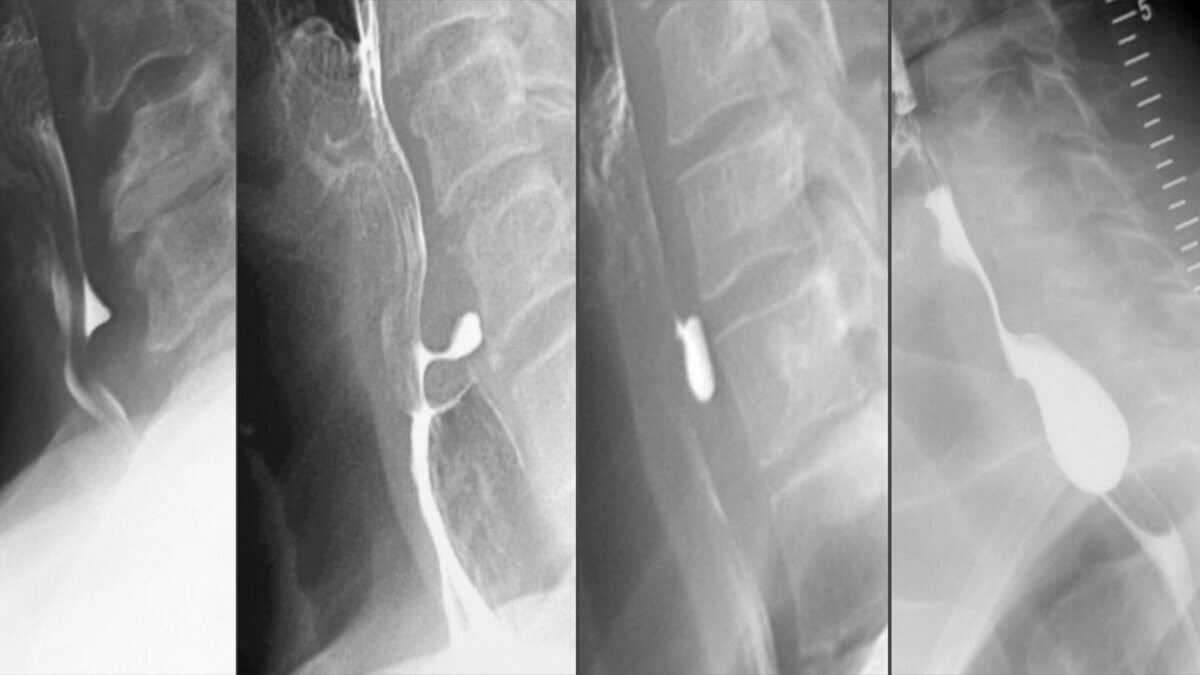

Der Ausprägungsgrad eines Zenker-Divertikels wird nach der Brombart-Klassifikation wie folgt eingeteilt:

| Grad | Charakteristik |

|---|---|

| 1 | 2-3 mm tiefe, dornenförmige Ausbuchtung |

| 2 | bis zu 8 mm lange, keulenförmige Aussackung |

| 3 | über 10 mm langes, sackförmiges, nach kaudal umgeschlagenes Divertikel ohne Kompression des Ösophagus |

| 4 | Divertikel mit großer Aussackung und Kompression des Ösophagus |

Bei der körperlichen Untersuchung fällt in manchen Fällen eine Schwellung im lateralen Bereich des Halses auf. Die definitive Diagnose ist mit einer Ösophaguspassage mit dem Kontrastmittel Barium (Ösophagusbreischluck) zu stellen.